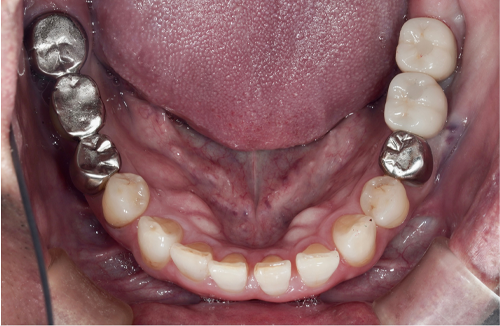

当院のインプラント治療例

― 他院で「難しい」と言われたケースにも対応 ―

当院では、インプラント治療を行うにあたり歯を失ったところだけではなくお口の中を全体的に検査をします。

その後、コンピューターでシュミレーションを行い、安全でより精度の高いインプラント治療を行っていきます。

インプラントは天然歯よりも感染に弱いため、長く持たせるためにはインプラント周囲の環境を整えることが大変重要になってきます。当院では必要に応じて失われた顎骨・歯肉の再建を行い、予知性の高いインプラント治療を行っていきます。

インプラント治療において私達が大切にしていることは、なぜ歯を失ってしまったかを徹底的に診断することです。

「虫歯で歯を失ってしまったのか?」、「歯周病で歯を失ってしまったのか?」、「かみ合わせの問題があるのかどうか?」等を診断することは非常に大事なことなのです。これらの事は、歯を失ったことは同じですが状況は全く異なるのです。

私達は歯を失ってしまった原因を追求し、インプラント治療、虫歯治療、歯周病治療、矯正治療、根管治療等の治療を組み合わせ総合的に治療計画を立てて治療を行っていきます。